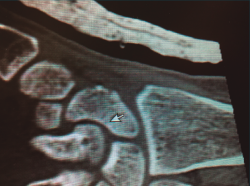

Figura 3. Visión fractura de escafoides por vía anterior.

Por vía abierta, podemos acceder por vía volar tal como describieron Russe en 1960(16) y Herbert en 1984(17). Se trata de un acceso relativamente fácil y adecuado a la lesión, que respeta al máximo la vascularización ósea; está indicada en las fracturas del tercio medio y tercio distal del escafoides. Nos permite una visión directa del foco de fractura controlando la reducción y la posterior síntesis (Figura 3).